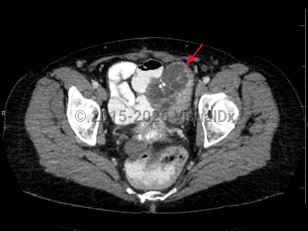

Rectal carcinomaRectal carcinoma

Psoas abscess

Bladder cancerBladder cancer